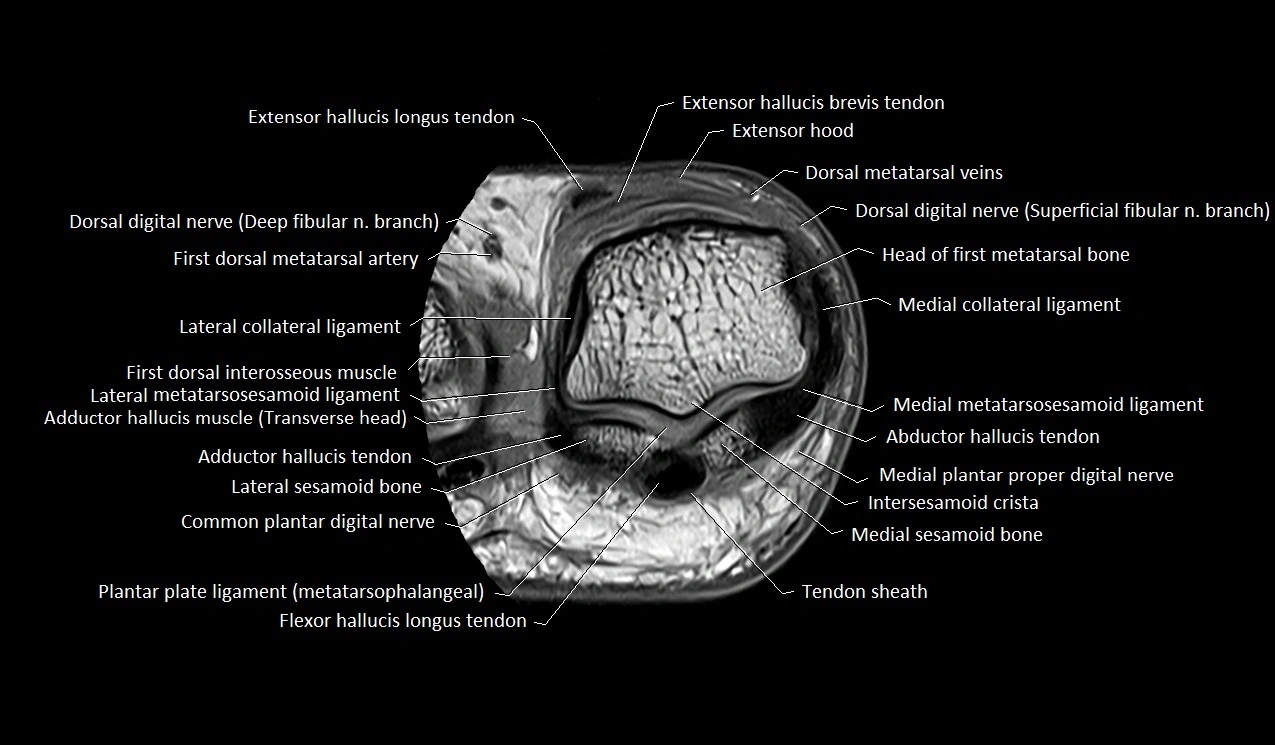

MRI image

image